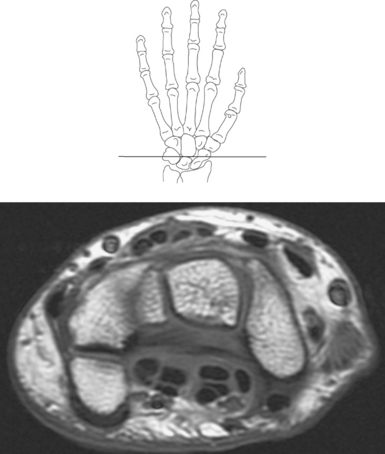

Numerous ligaments provide additional stability to the wrist. The extrinsic ligaments reinforce the joint cavity surrounding the carpal region and include palmar and dorsal radial carpal ligaments, the radial and ulnar collateral ligaments, and the TFCC (Figures 9.115 through 9.117). The many articulations between the carpal bones are supported by the intercarpal ligaments or intrinsic ligaments that connect the carpal bones to each other (Figure 9.115). The configuration of the intrinsic ligaments, metacarpal ligaments, and triangular fibrocartilage complex creates five different joint compartments that can be demonstrated at arthrography: (1) compartment of the first carpometacarpal articulation, (2) common carpometacarpal compartment, (3) mediocarpal compartment, (4) intermetacarpal compartment, and (5) radiocarpal compartment (Figure 9.115). The carpal tunnel is created by the concave arrangement of the carpal bones (Figure 9.103). A thick ligamentous band called the flexor retinaculum (transverse carpal ligament) stretches across the carpal tunnel to create an enclosure for the passage of tendons and the median nerve (Figures 9.118 through 9.120). The flexor retinaculum inserts medially on the pisiform and hook of the hamate and spans the wrist to insert laterally on the scaphoid and trapezium. In addition to the carpal tunnel, another tunnel called Guyon’s canal is formed where the ulnar extension of the flexor retinaculum continues over the pisiform and hamate. This creates a potential site for compression of the ulnar nerve (Figures 9.118, top, and 9.119). The extensor retinaculum (dorsal carpal ligament), located dorsally, is much thinner. It attaches medially to the ulnar styloid process, triquetrum, and pisiform and laterally to the lateral margin of the radius (Figure 9.120, left). Along its course it forms six fibroosseous tunnels for the passage of the synovial sheaths containing the extensor tendons (Figure 9.118, bottom).